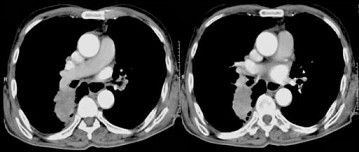

72岁,男,呼吸急促、气喘4个月,请结合胸片,选出最可能的诊断()

72岁,男,呼吸急促、气喘4个月,请结合胸片和CT,选出最可能的诊断()<img style="width: 199px; height: 208px;" src="

[单选题]72岁,男,呼吸急促、气喘4个月,请结合胸片和CT,选出最可能的诊断()A.肺癌B.错构瘤C.肺结核D.韦格肉芽肿E.支气管腺瘤

患者72岁,男,呼吸急促、气喘4个月,结合胸片和CT,最可能的诊断是<img border="0" style="width: 300px; height: 208

[单选题]患者72岁,男,呼吸急促、气喘4个月,结合胸片和CT,最可能的诊断是A.肺癌B.错构瘤C.肺结核D.韦格肉芽肿E.支气管腺瘤

72岁,男,呼吸急促、气喘4月,结合胸片和CT,最可能的诊断是()<img border="0" style="width: 366px; height: 275p

[单选题]72岁,男,呼吸急促、气喘4月,结合胸片和CT,最可能的诊断是()A.肺癌B.错构瘤C.肺结核D.韦格肉芽肿E.支气管腺瘤

患者72岁,男,呼吸急促、气喘4个月,结合胸片和CT,最可能的诊断是( )。<br /><img border="0" style="width: 2

[单选题]患者72岁,男,呼吸急促、气喘4个月,结合胸片和CT,最可能的诊断是( )。图1图2图3图4A.肺癌B.错构瘤C.肺结核D.韦格肉芽肿E.支气管腺瘤

72岁,男,呼吸急促、气喘4个月,请结合胸片和CT,选出最可能的诊断()

[单选题]72岁,男,呼吸急促、气喘4个月,请结合胸片和CT,选出最可能的诊断()A . 肺癌B . 错构瘤C . 肺结核D . 韦格肉芽肿E . 支气管腺瘤